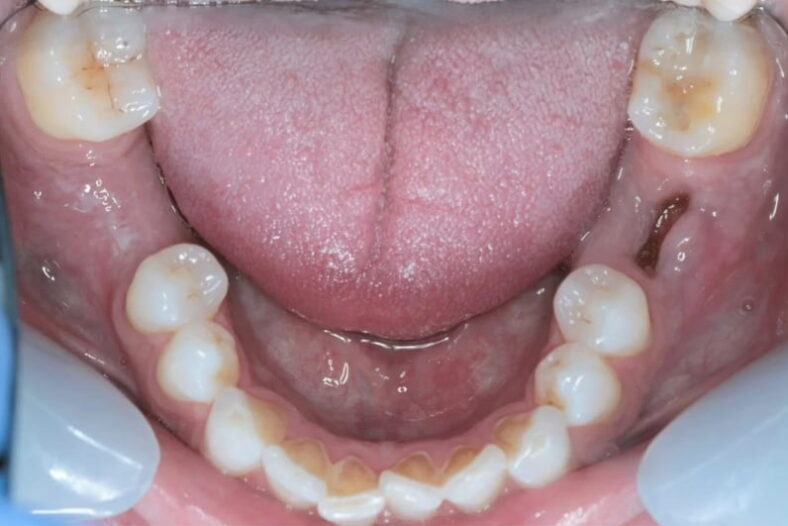

This patient lost his two of his lower molar teeth. Implants were placed on either side to replace…